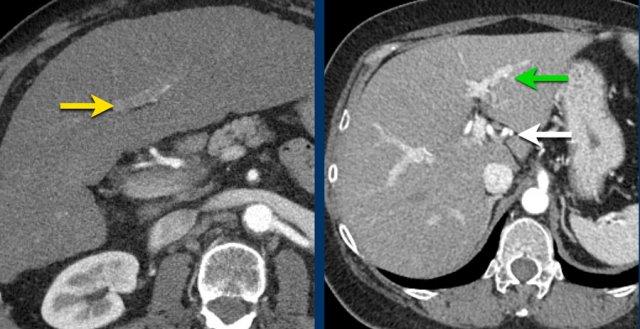

Đây là hình ảnh thì động mạch muộn của một bệnh nhân xơ gan.

Ghi nhận một tổn thương có tăng ngấm thuốc không dạng viền (mũi tên vàng).

Ở thì muộn, tổn thương có hiện tượng washout.

Đây là những đặc điểm điển hình của HCC.

Tổn thương còn lại (mũi tên xanh lá) là tổn thương đã được điều trị, sẽ được thảo luận ở phần sau.

Washout – Vỏ bao

Đây là một bệnh nhân khác với tổn thương có ngấm thuốc và hiện tượng washout.

Lưu ý vỏ bao ngấm thuốc trên thì muộn.

Vỏ bao là một trong những đặc điểm chính của HCC và có thể hoàn toàn hoặc một phần.

Vỏ bao cần được tính vào trong phép đo kích thước của tổn thương.